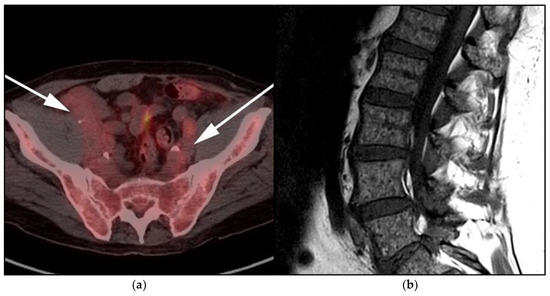

Figure 11.

A 85-year-old-male with known diagnosis of lymphoplasmacytic lymphoma (LPL). (a) Maximal intensity projection (MIP) FDG PET/CT image shows extensive hypermetabolic uptake within the spine, pelvis, and proximal upper and distal appendicular skeleton (white arrows). This patient had not received recent marrow stimulating drugs, which can produce imaging findings consistent with marrow infiltration (b). A sagittal CT image shows diffuse osteopenia, marrow space widening, and no discrete focal lesions (black arrows). This is a very important to differentiate from myeloma, which often presents with frankly lytic lesions.

WM patients can also present with splenomegaly with or without focal lesions and lymphadenopathy typically within the axillary, retroperitoneal, and/or inguinal nodal stations (Figure 12). Cranial nerve deficits can be a manifestation of Bing–Neel syndrome, a rare CNS manifestation seen in WM disease [45,48,52,54]. In Bing–Neel syndrome, neurological symptoms can be directly related to infiltration by lymphoplasmacytic cells or indirectly result from the deposition of circulating IgM immunoglobulin on the brain parenchyma, spinal cord, or cranial or peripheral nerves (Figure 13). Additionally, 18F-FDG PET/CT plays an important role in monitoring therapeutic response after treatment initiation, especially with rituximab. WM patients tend to show elevated IgM levels, known as an IgM flare, which may mimic progressive disease. Imaging plays a pivotal role to differentiate between an IgM flare and true progression, thus obviating the need for repeated marrow biopsy [52]. Imaging may also help in excluding the development of myelodysplastic syndromes, acute leukemia, or DLBCL transformation [52].

Multimodality imaging, including CT, MRI, and/or 18F-FDG PET/CT, is essential for initial diagnosis, especially in extramedullary disease presentation. Imaging can be helpful in determining optimal biopsy sites, as well as the assessment of response to therapy and monitoring disease progression or transformation. Unlike MM, WM is not associated with definite osseous lytic lesions, a feature that can distinguish WM from MM. WM usually manifests as osteopenia, marrow space widening, and endosteal erosions [52,53] (Figure 11).